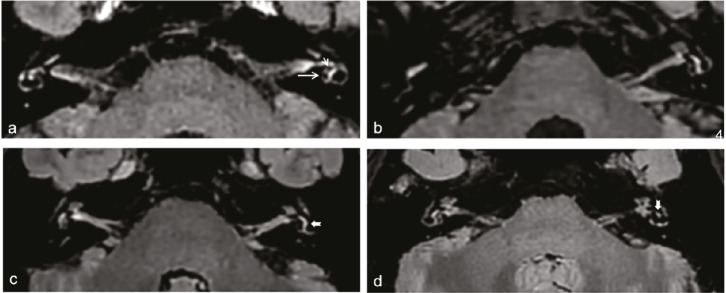

Purpose: To evaluate the diagnostic performance of delayed post-gadolinium enhancement magnetic resonance imaging (DEMRI) in diagnosing Menière’s disease (MD) and to establish an effective MRI-based diagnostic model.

Methods: This retrospective multicenter study assessed DEMRI descriptors in patients presenting with Ménièriform symptoms who were examined consecutively between May 2022 and May 2024. A total of 162 ears (95 with MD, 67 controls) were included. Each ear was randomly assigned to either a training set (n = 98) or a validation set (n = 64). In the training cohort, diagnostic models for MD were developed using logistic regression. The area under the curve (AUC) was used to evaluate the diagnostic performance of the different models. The Delong test was applied to compare AUC estimates between models.

Results: The proposed DEMRI diagnostic model demonstrated strong diagnostic performance in both the training cohort (AUC: 0.907) and the validation cohort (AUC: 0.887), outperforming the clinical diagnostic model (P = 0.01231; 95% confidence interval: 0.033–0.269) in the validation cohort. The AUC of the DEMRI model was also higher than that of the combined DEMRI-clinical model (AUC: 0.796), although the difference was not statistically significant (P = 0.054). In the training set, the sensitivity and specificity of the DEMRI model were 78.9% and 88.5%, respectively.

Conclusion: A diagnostic model based on DEMRI features for MD is more effective than one based solely on clinical variables. DEMRI should, therefore, be recommended when MD is suspected, given its significant diagnostic potential.

Abstract Image